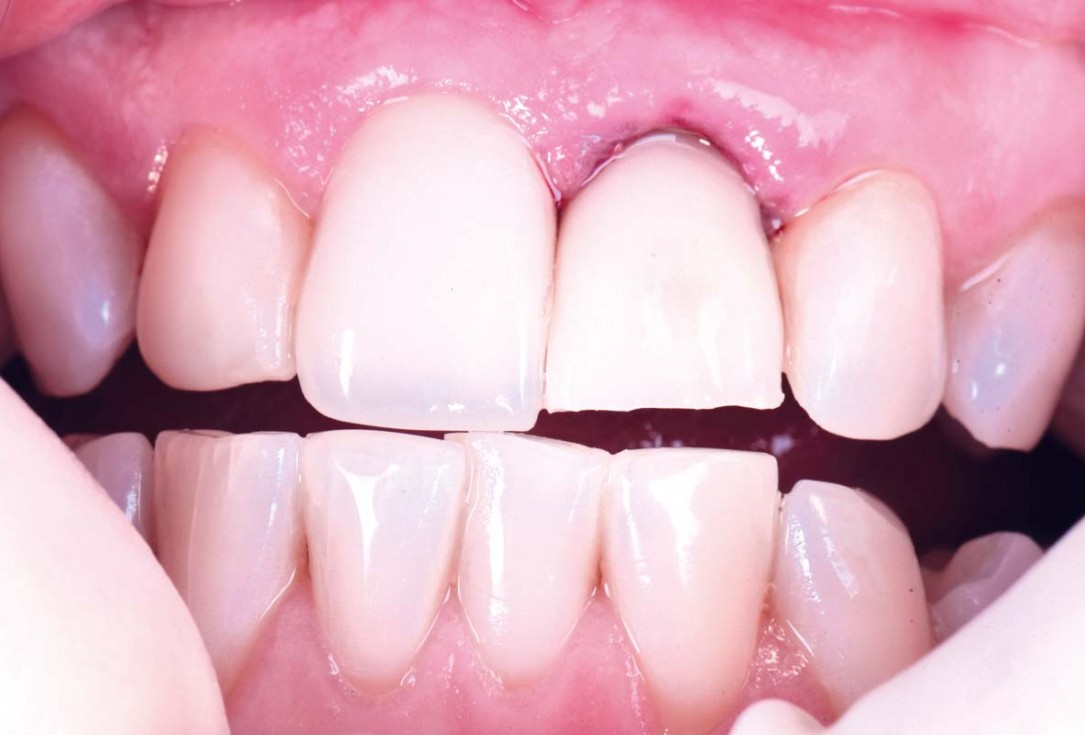

01/30 - Initial situationExcellent aesthetic result of buccal augmentation with mucoderm® and maxgraft® after immediate implant placement - 3-years follow-up - Dr. A. Puišys

02/30 - Initial situation, 36 year old ladyExcellent aesthetic result of buccal augmentation with mucoderm® and maxgraft® after immediate implant placement - 3-years follow-up - Dr. A. Puišys